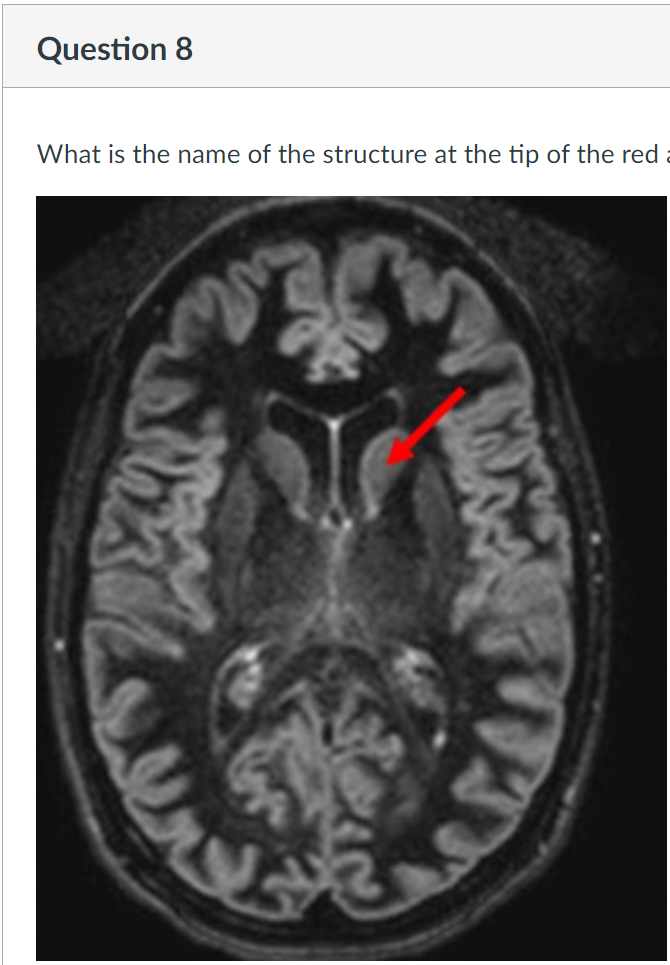

8

Q

A

choroid plexus